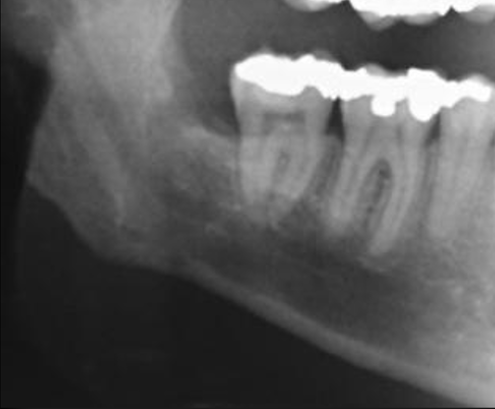

Negli anni 1997 e ’98 nel reparto di Chirurgia Speciale Odontostomatologica da me diretto all’Università degli Studi di Bologna su 262 pazienti deputati ad estrazione del dente del giudizio inferiore, abbiamo rilevato dalla ortopantomografia (OPT) 37 casi dubbi e di questi l’esame Tac, successivamente effettuato, ha dimostrato un effettivo coinvolgimento delle radici del dente con il nervo mandibolare in 31 pazienti, cioè nell’84% dei casi.

Esami radiografici quali, lastre endorali, OPT e Tac sono richiesti al fine di valutare la difficoltà ed il rischio estrattivo.